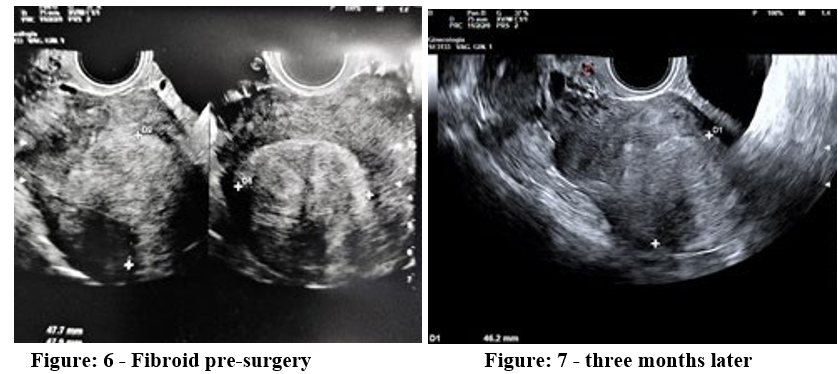

Of course, the reduction of myoma volume is important but we believe that the structural modification and the healing process are more important. In some cases we have seen the thermos-ablat-ed myoma that no longer shows its boundaries separating it from the surrounding myometrium. The ultrasound examination, a few months after the thermal ablation, shows us a myoma with ultra¬sound characteristics similar to those of the healthy myometrium Figure 6,7. This aspect leads us to think of a more suitable recov¬ery for the establishment of a future pregnancy.